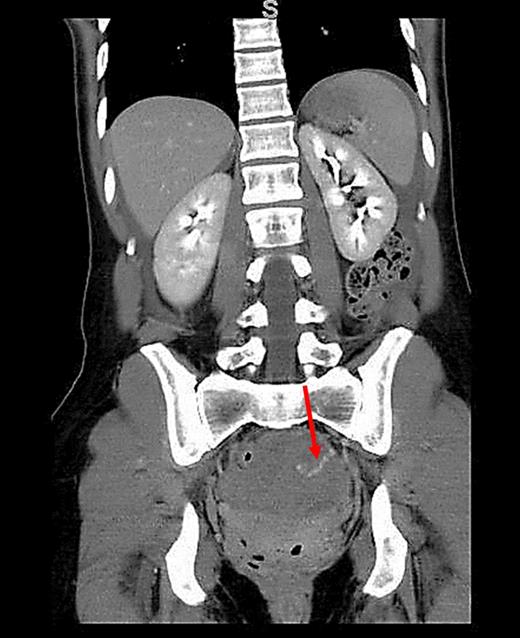

A 34-year-old female with no past medical history was transferred to our emergency department from an outside hospital due to concern for intra-abdominal bleeding. She initially presented with lower abdominal pain immediately following vaginal intercourse described as nonvigorous with the patient mostly ‘on top’, and no history of foreign body use or trauma. CT of the abdomen and pelvis with IV contrast performed at the outside hospital revealed an intra-abdominal hematoma with extravasation of contrast questionably from one of the branches of the left internal iliac artery (Figs 1 and 2). No adnexal lesions were identified on the CT. Upon arrival, the patient was complaining of constant, sharp, severe bilateral lower quadrant abdominal pain, nausea and fatigue. There was no history of loss of consciousness, vomiting, vaginal or rectal bleeding, or hematuria. A past surgical history consisted of appendectomy. Her last menstrual period was 19 days prior to presentation.

CT (coronal view) of the abdomen and pelvis showing extravasation of contrast material into the left pelvis (red arrow).